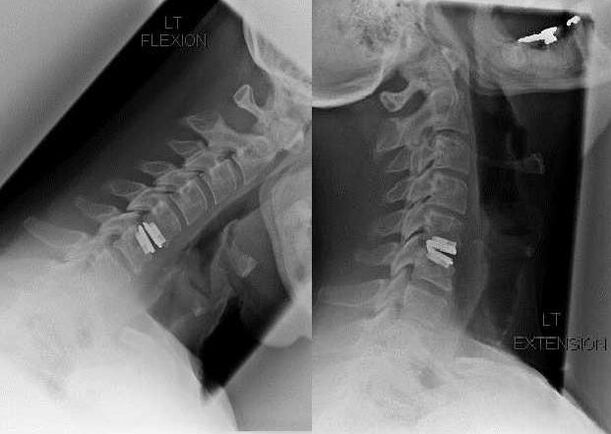

Las indicaciones para la intervención quirúrgica incluyen la ineficacia del tratamiento conservador y las complicaciones de la osteocondrosis cervical, por ejemplo, mielopatía discogénica, síndrome de la arteria vertebral y síndrome radicular. Para aliviar la carga sobre la médula espinal, los vasos sanguíneos y las raíces espinales, se realizan las siguientes operaciones:

- laminectomía;

- laminotomía;

- foraminotomía;

- facetectomía;

- Discectomía.

Durante la cirugía, se pueden extirpar fragmentos de hueso y ligamentos y se pueden extirpar total o parcialmente los discos intervertebrales. Para pequeñas protuberancias de hernia, a menudo se realiza la vaporización con láser del núcleo del disco.

Después de la extirpación de las estructuras vertebrales, a menudo se requiere la estabilización de los segmentos móviles de la columna mediante fusión espinal o la instalación de autoinjertos de hueso y piel.